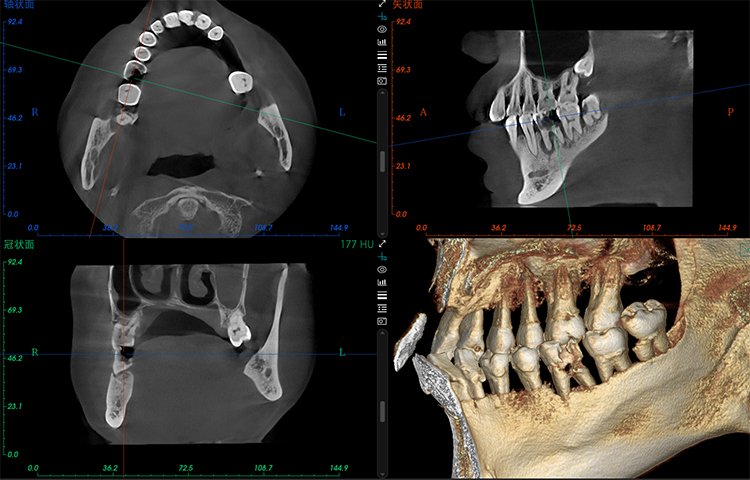

- Amplio campo de visión, satisfaciendo las necesidades clínicas generales.

- Potente funcionalidad, mejorando fácilmente la eficiencia clínica.

El software de diagnóstico 3D líder de Meyer y el sistema de análisis ortodóntico inteligente adoptan un diseño de UI modular, lo que hace que las funciones del software sean más cercanas a las necesidades clínicas y más fáciles de usar para los médicos, reduciendo significativamente el costo de aprendizaje.

Software de Diagnóstico 3D

MyDentViewer